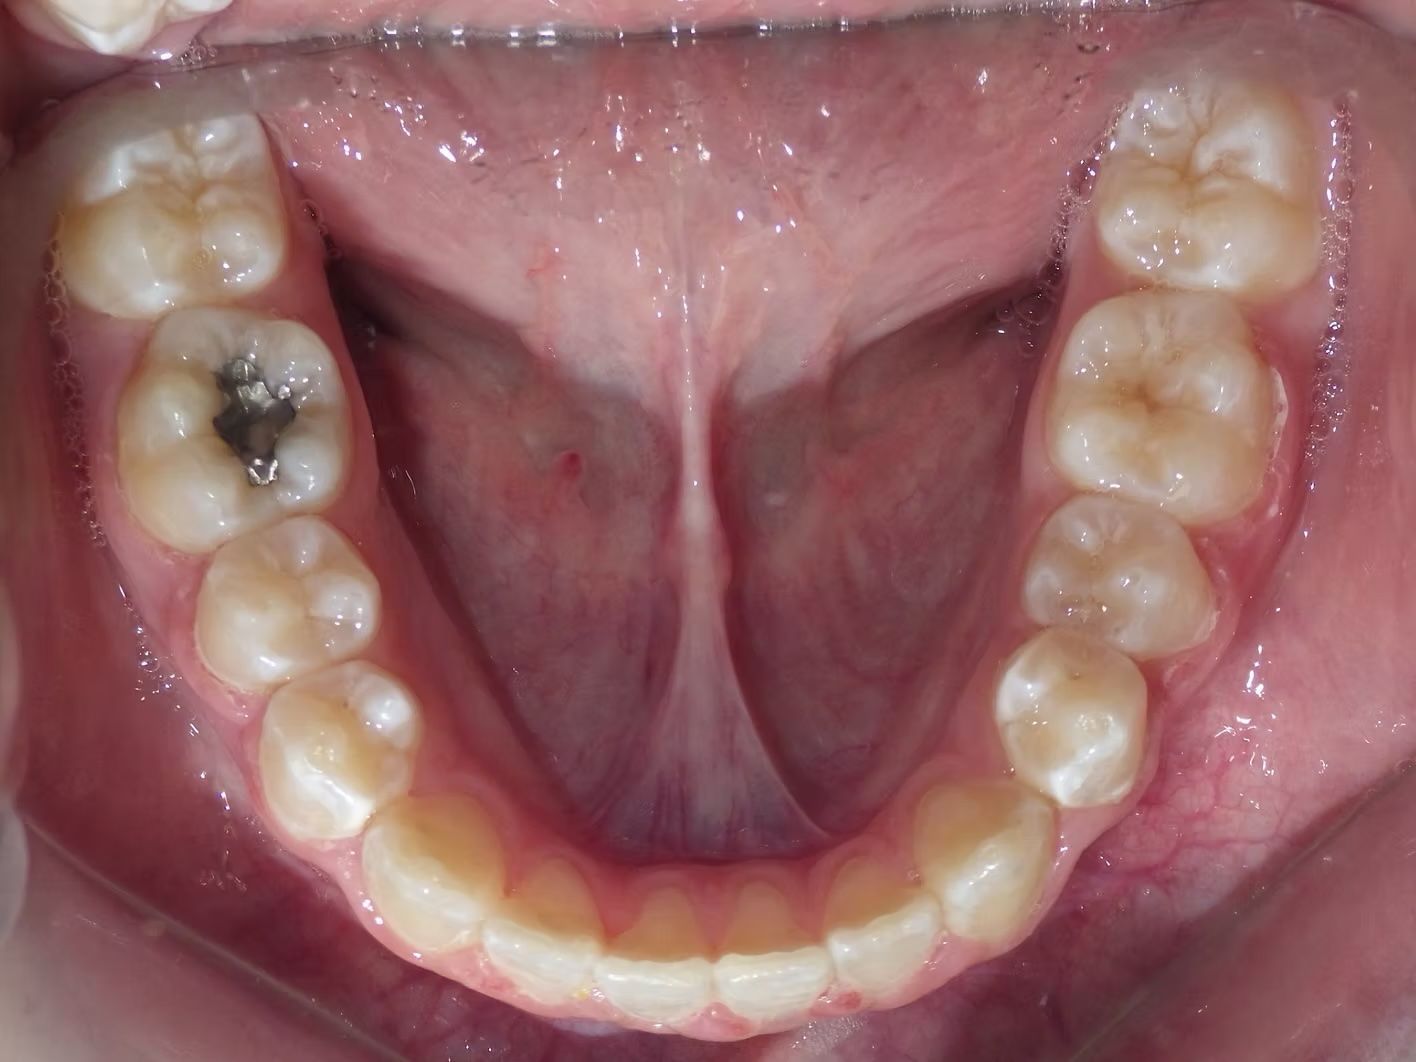

Imset

Imset came to see Dr. Bret because he felt like the upper and lower teeth were too crowded. The lower canines were in cross-bite with the upper teeth and there was significant crowding in the lower arch. He previously had 2 teeth pulled in the top and at the time none in the bottom. This made the top jaw smaller than the lower and the lower teeth didn't have room to fit inside the top teeth. We had 2 lower teeth extracted, and then aligned the upper and lower teeth to fit excellently together- no more crowding!